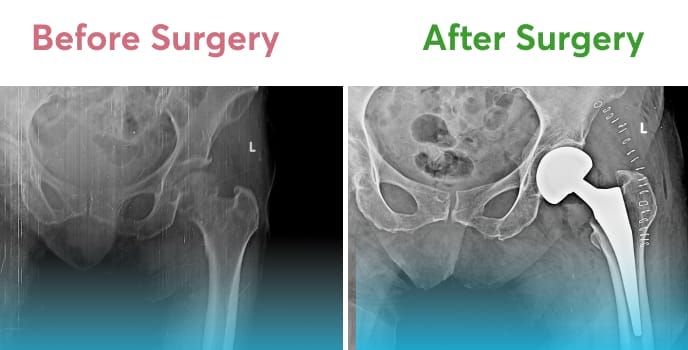

A joint is any place in your body where two bones meet. One of the most important joints is the hip joint, which connects your upper and lower body. The hip joint is a ball-and-socket joint and one of the largest joints in the body, comprising your pelvis (hip bone) and femur (thigh bone). This joint enables your legs to support your body weight and offers a wide range of motion for your legs and hips.